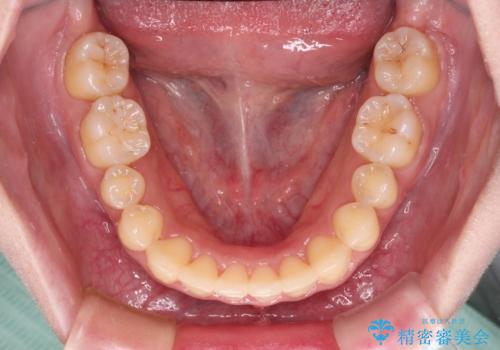

- 前歯のデコボコを気にして来院された患者様です。

上顎右側犬歯が八重歯になっており、それによって奥歯が前方に移動しているため、右側の咬み合わせの改善が必要と判断されました。

より治療を速やかに行うため、上顎右側にアンカースクリューを使用し、目標としていた1年半ほどで治療を終えることができました。